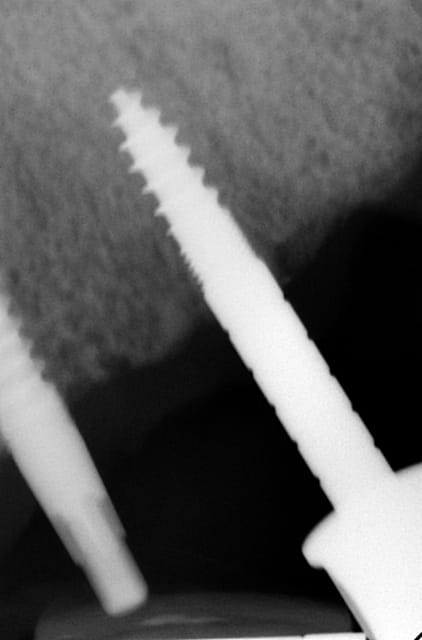

Les deux premières photos montrent le cas d´une jeune femme ( qui malheureusement s est fait retiré toutes les dents à l´étranger....).Ce cas a pu être terminé deux semaines après l´implantation.

Les forets utilisés ont 3 faces et sont coniques (250 trs/min) permettent une condensation de l´os et un traitement minimalement invasif.